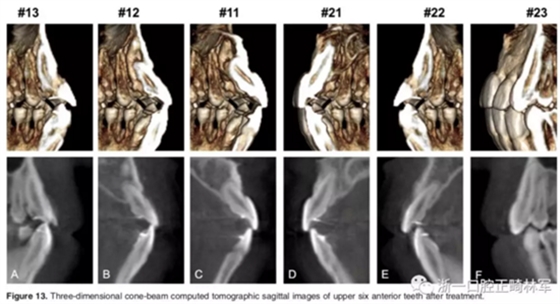

影像學:頭顱側位片示:矢狀向和垂直向骨骼發(fā)生變化(ANB角,3°;SN-MP,51°);上頜切牙略前傾(U1-SN,106°),與下頜切牙一致(IMPA,75°);病人的面部輪廓得以保持。全景片示:由于牙齒萌出,上前牙區(qū)垂直向牙槽骨水平增加;雖然前牙牙根較彎曲,但其平行度仍可,且無明顯的牙根吸收。CBCT示:前牙唇側骨質連續(xù)性改善,牙根唇側支持組織變好,牙槽骨高度、厚度均有增加,但轉矩的改變一定程度上導致了局部應力的增大。